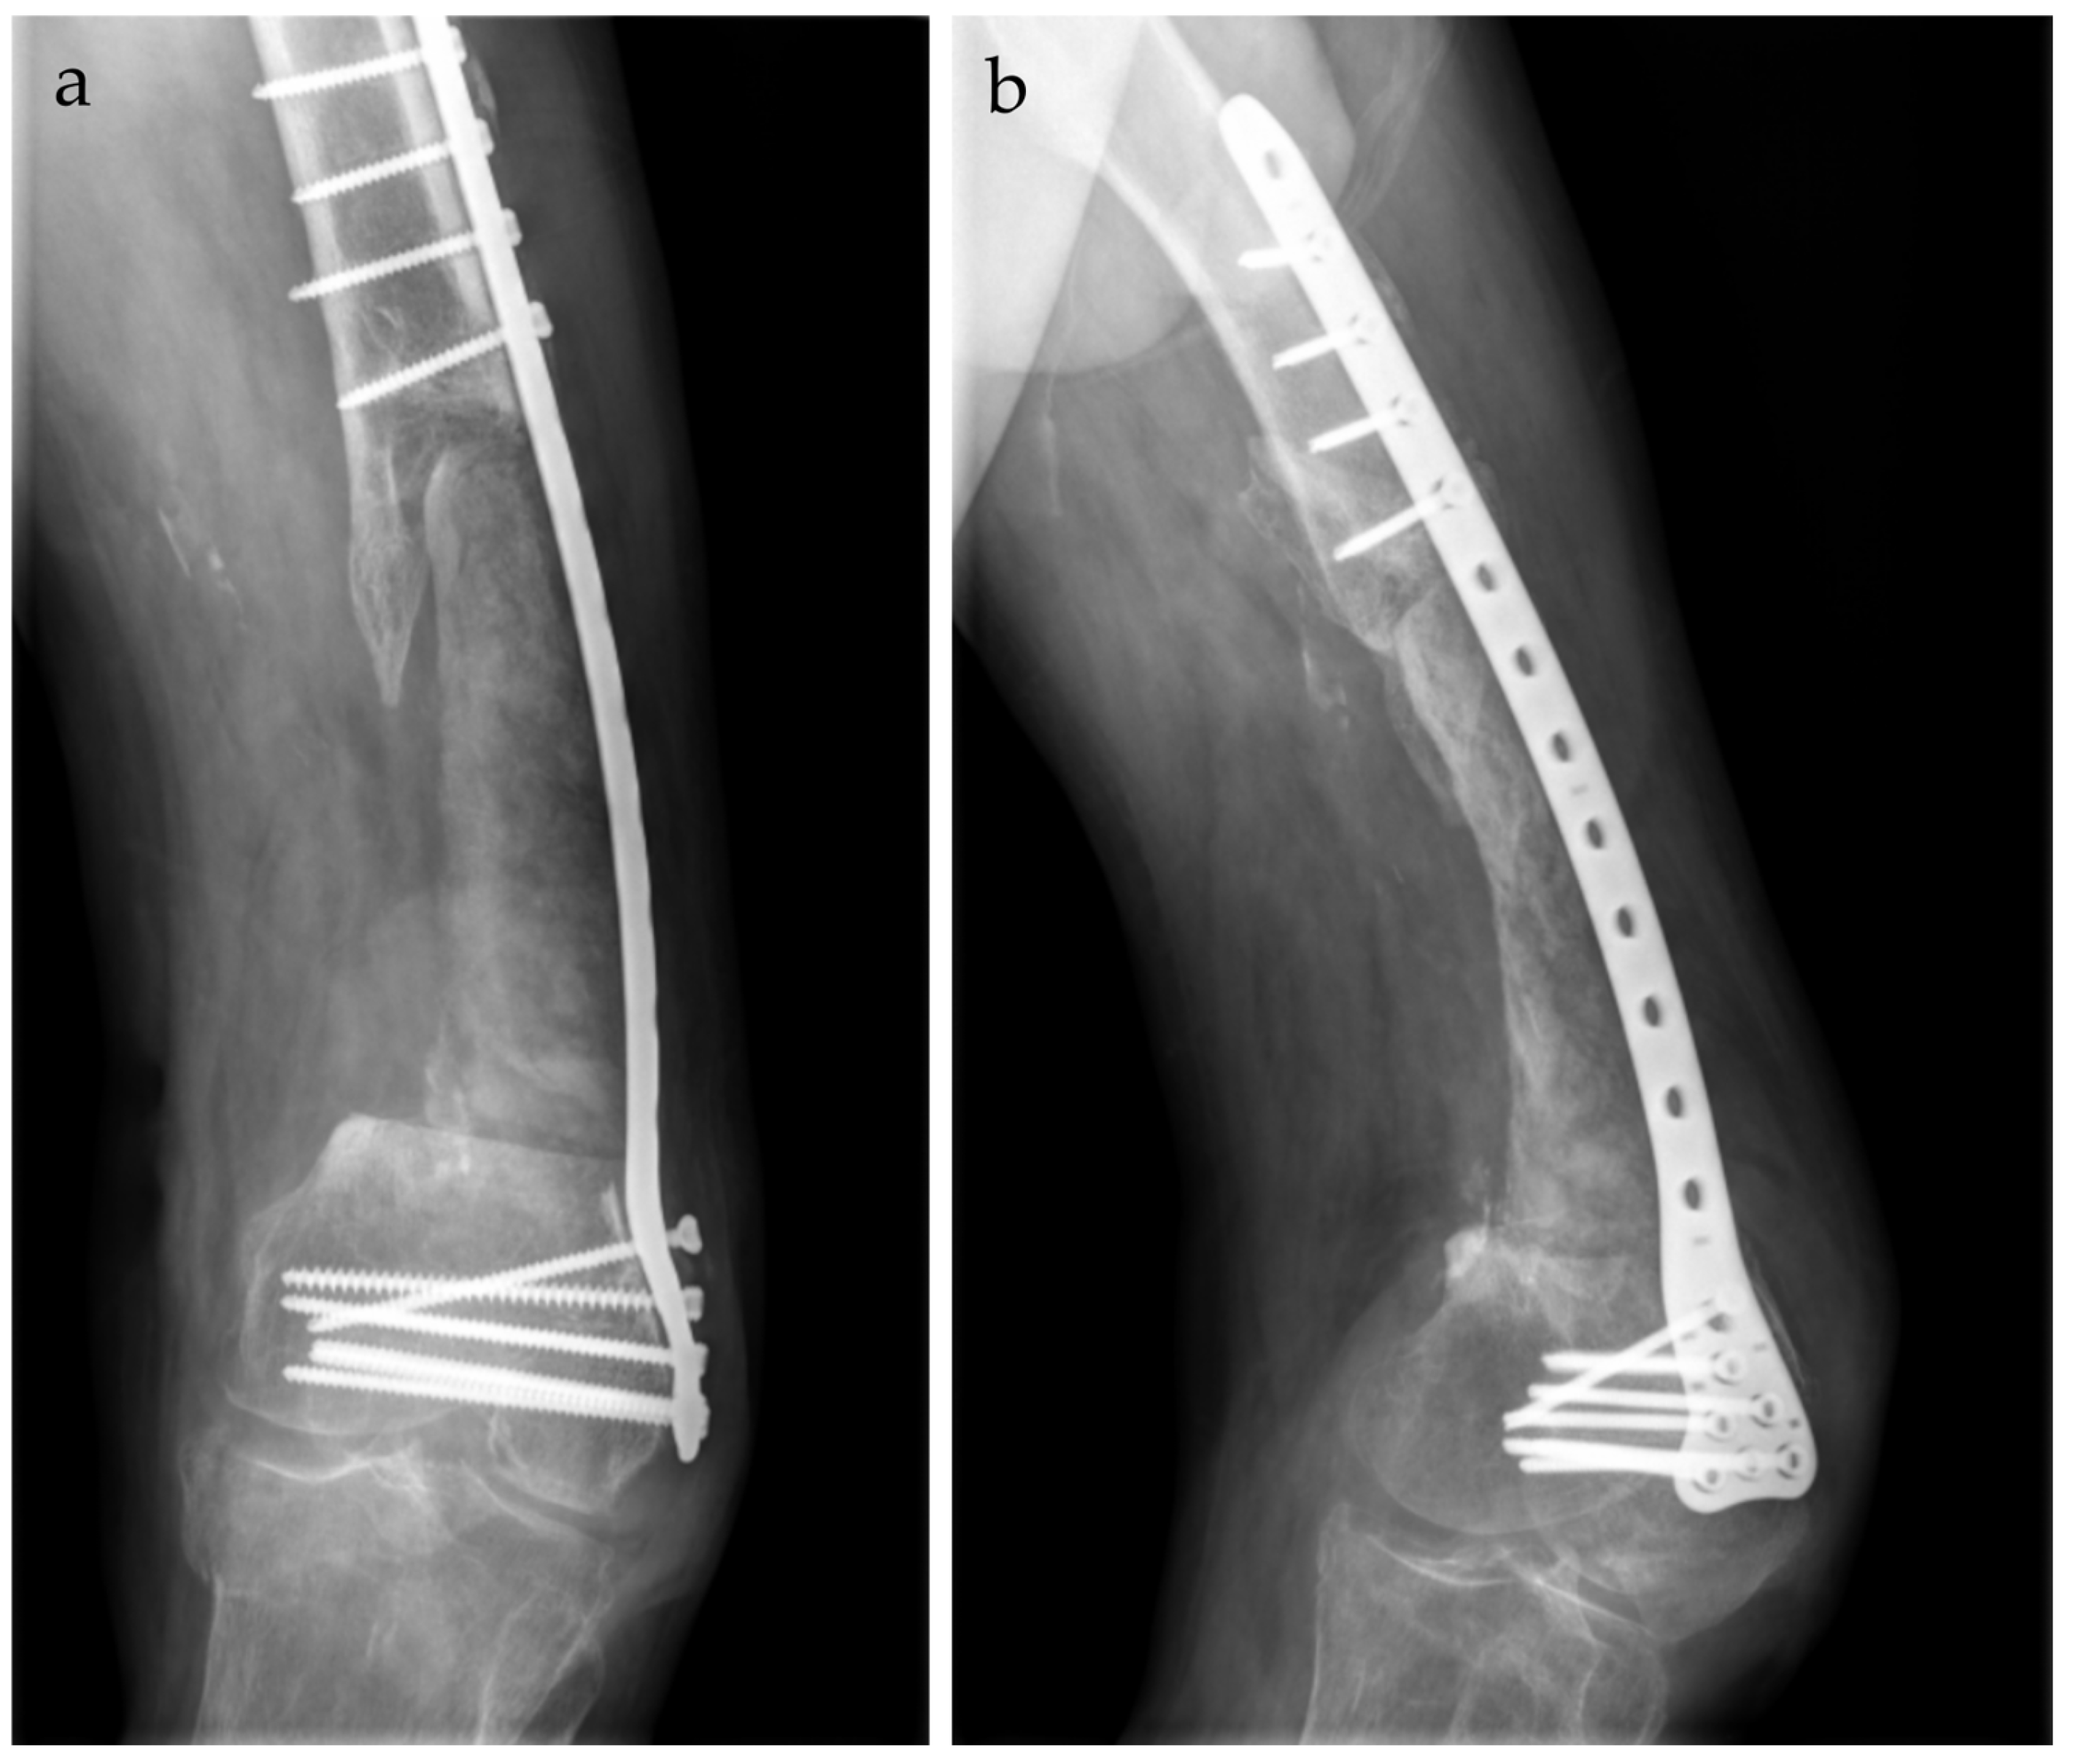

2. Case Report